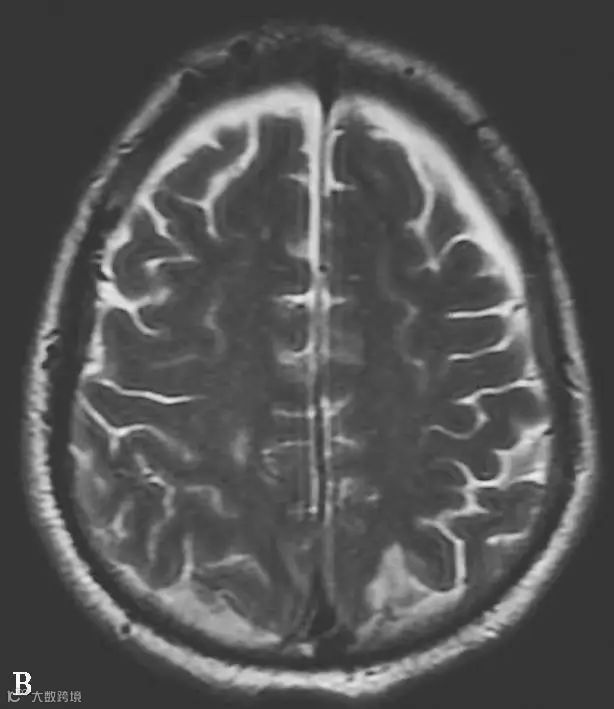

图6-11-1 弥漫性轴索损伤并双侧额部硬膜下积液、双侧顶枕部硬膜下血肿

男,34岁,外伤后7天。A~H(A、B.T2WI,C、D.T1WI,E、F.T2WI-FLAIR,G、H.DWI):左侧岛叶及右侧顶叶白质可见斑片状稍长T1稍长T2信号,边缘不清,FLAIR及DWI呈高信号。双侧额部内板下可见新月形长T1长T2信号,FLAIR及DWI呈低信号。双侧顶枕部内板下可见弧形短T1长T2信号,FLAIR及DWI呈高信号